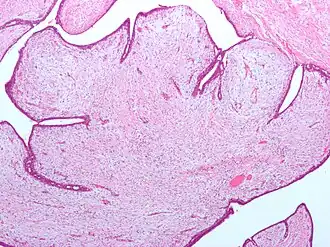

Coupe histologique colorée (H&E) d'une tumeur phyllode.